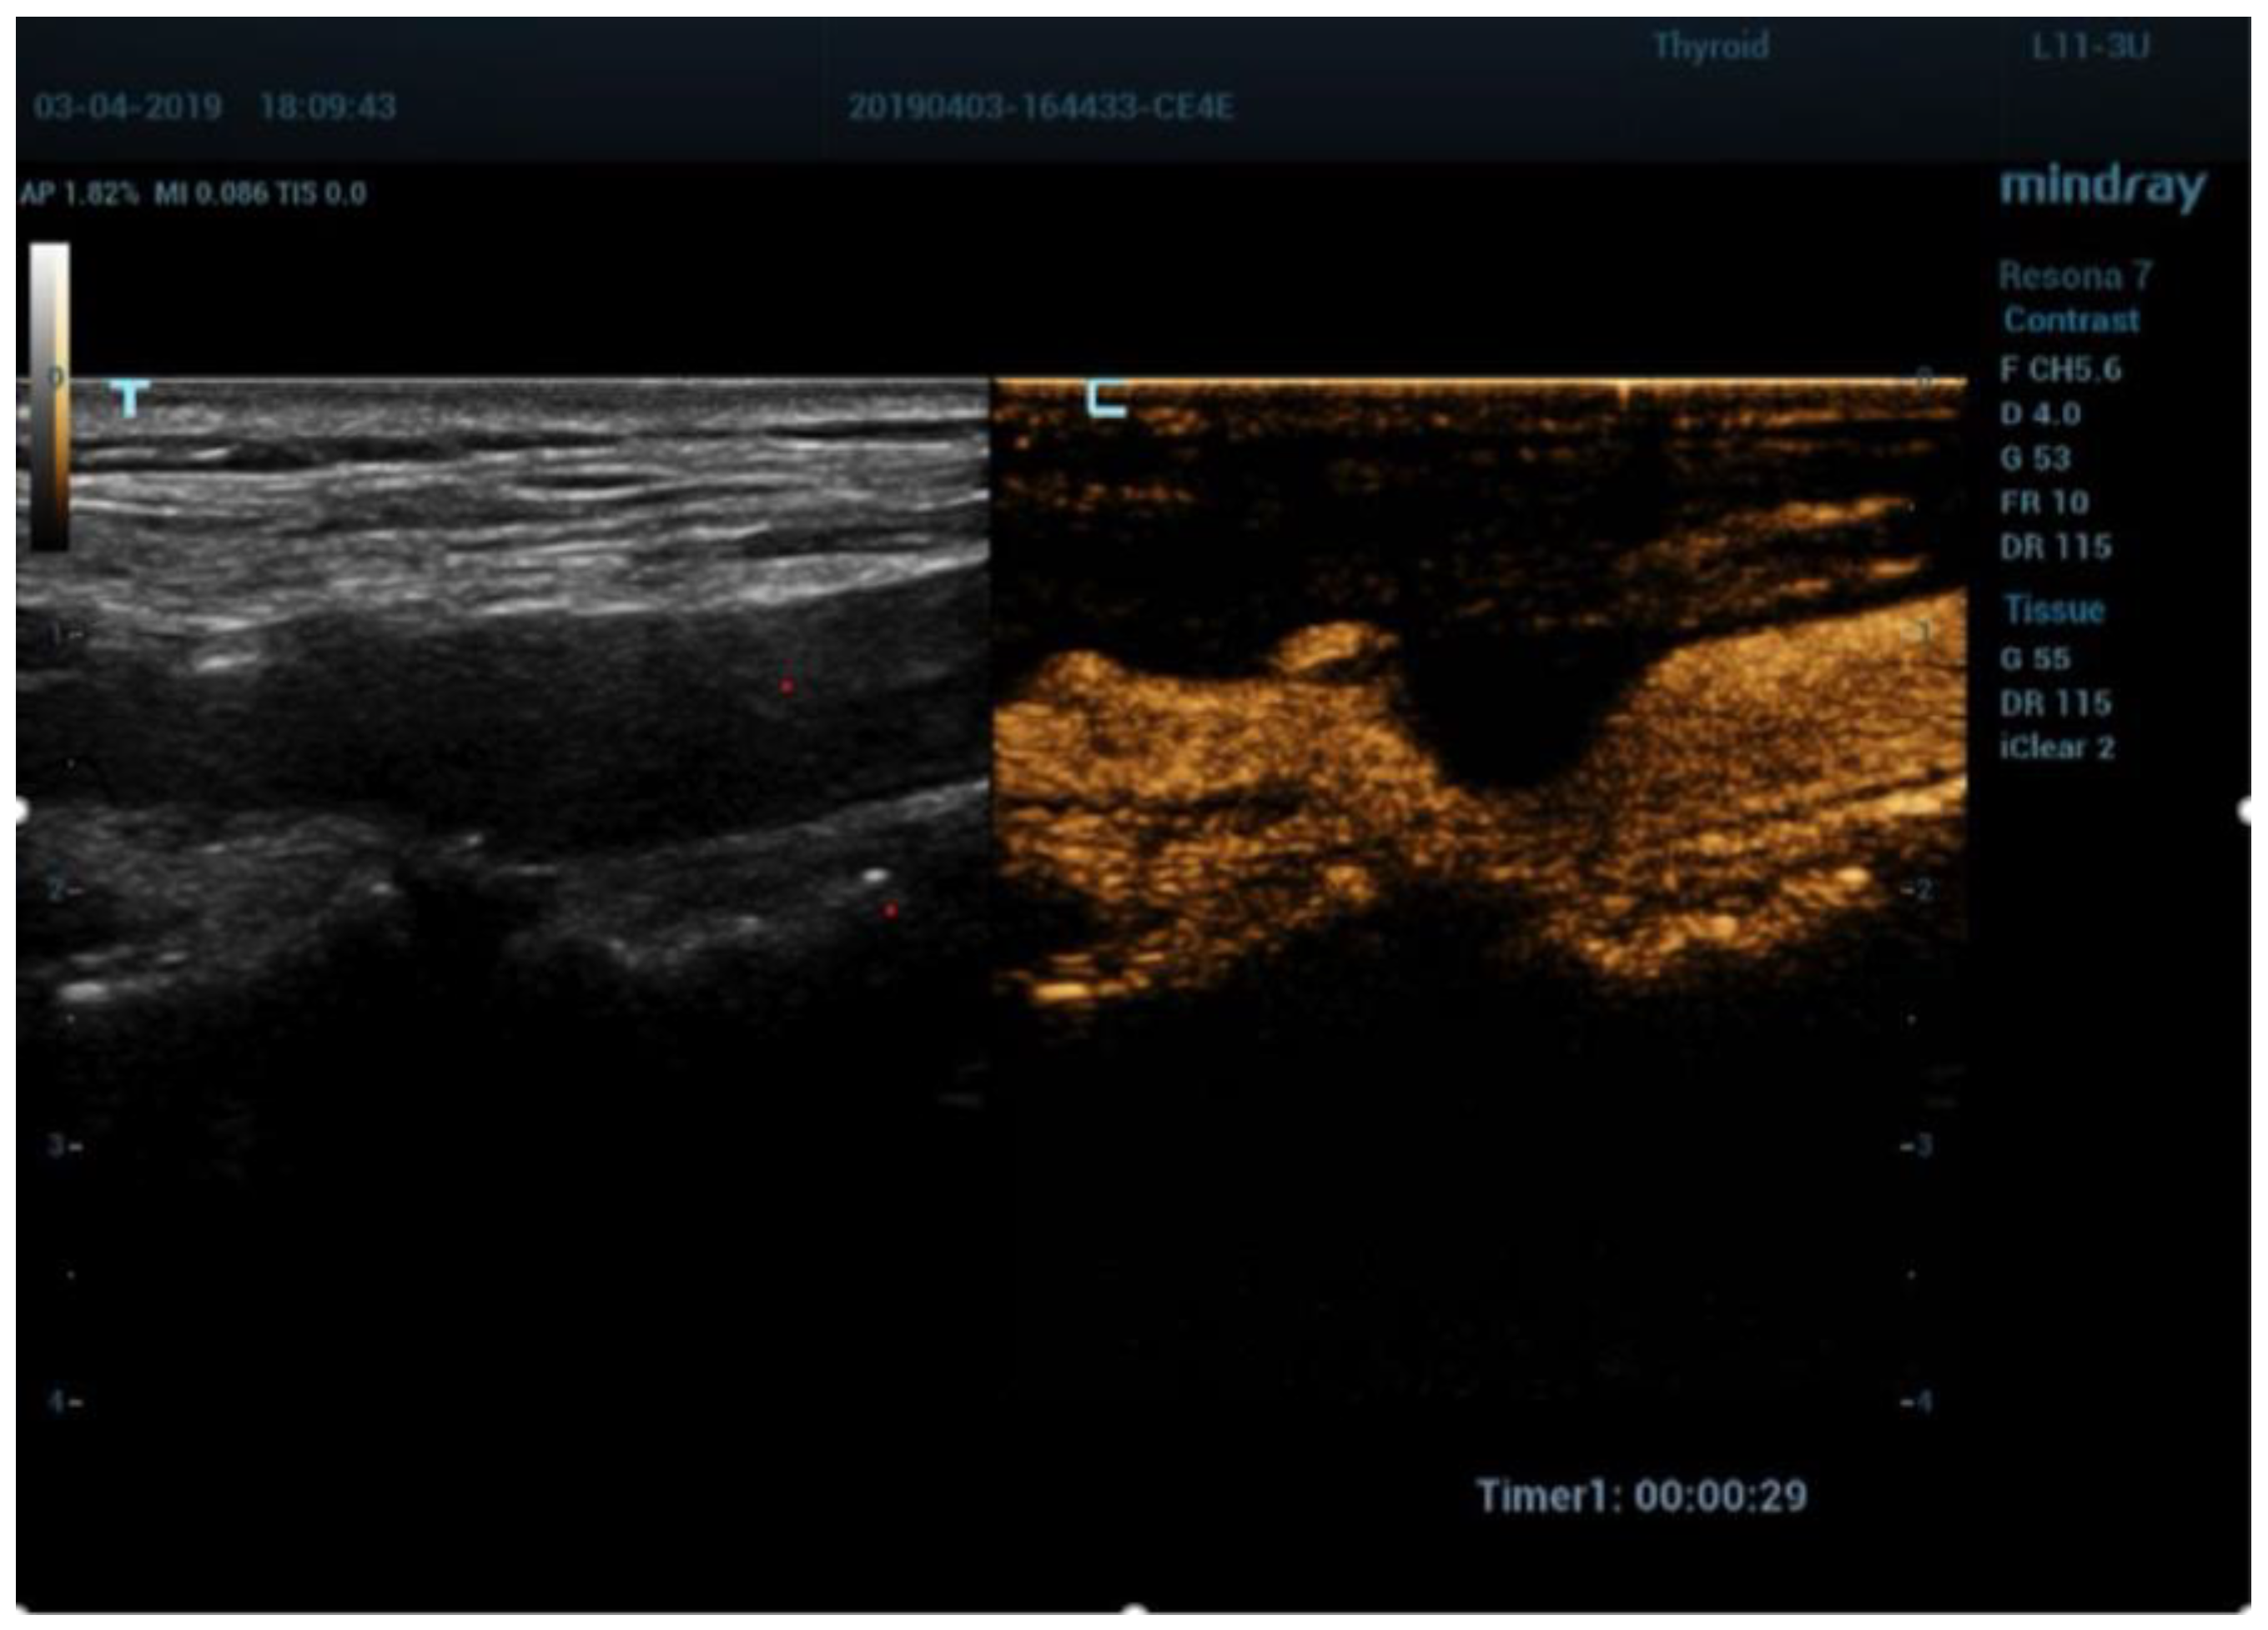

5. Contrast Enhanced Ultrasound (CEUS)

- Fresilli, D.; Di Leo, N.; Martinelli, O.; Di Marzo, L.; Pacini, P.; Dolcetti, V.; Del Gaudio, G.; Canni, F.; Ricci, L.I.; De Vito, C.; et al. 3D-Arterial analysis software and CEUS in the assessment of severity and vulnerability of carotid atherosclerotic plaque: A comparison with CTA and histopathology. Radiol. Med. 2022, 127, 1254–1269. [Google Scholar] [CrossRef] [PubMed]

- Clevert, D.A.; Sommer, W.H.; Helck, A.; Saam, T.; Reiser, M. Improved carotid atherosclerotic plaques imaging with contrast-enhanced ultrasound (CEUS). Clin. Hemorheol. Microcirc. 2011, 48, 141–148. [Google Scholar] [CrossRef] [PubMed]